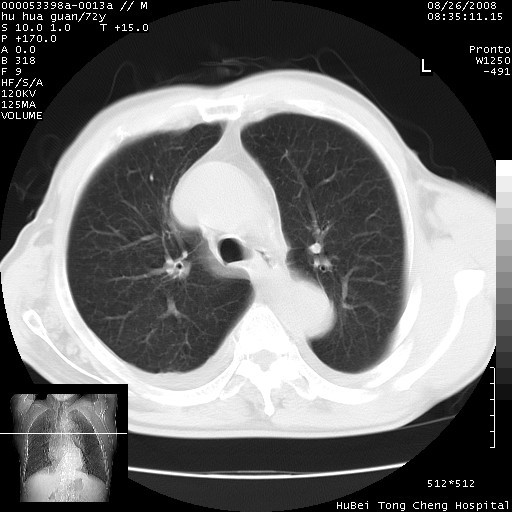

1、右上肺结节病变,肺泡癌不除外,请随诊;左下肺近后纵隔病变,考虑纵隔型肺癌侵犯大血管可能;

2、右下肺背段少许炎症,双侧胸腔积液,右下肺纤维索条。

降主动脉前移位,后纵隔占位

后纵隔占位,降主动脉前移位;双侧胸腔积液;应排外食管病变侵犯血管可能;